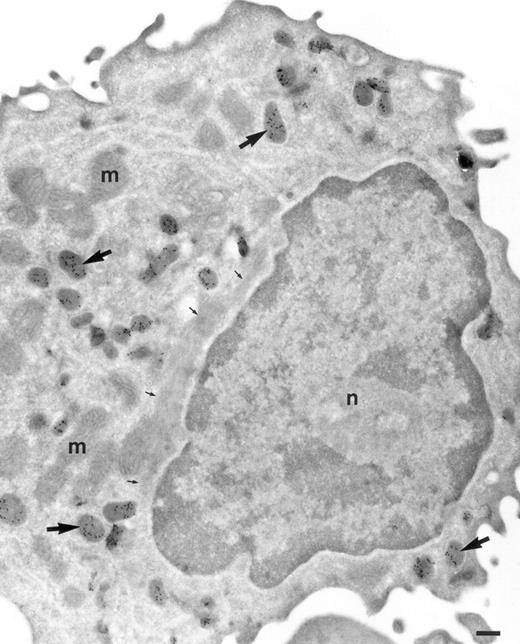

Localization of TGF-α in promonocytes. Ultrathin cryosection of a promonocyte of the bone marrow labeled to detect TGF-α. Many granules are present strongly labeled for TGF-α (large arrows). Mitochondria (m) and nucleus (n) are negative. Small arrows are pointing to a large bundle of filaments characteristic for promonocytes. Bar = 300 nm.

In promonocytes from the bone marrow, as well as monocytes from bone marrow and peripheral blood, TGF-α was localized in abundant electron-dense granules (Figs 1 and 2). The pattern of granules was similar in bone marrow promonocytes (Fig 1) and mature monocytes (Fig 2). These cells can be distinguished by the presence of bundles of filaments in the cytoplasm and a rounded or oval nucleus in promonocytes. Indications for the release of TGF-α–positive granules came from monocytes incubated for 24 hours with IL-10 and IFN-γ and thereafter labeled with anti–TGF-α. At the ultrastructural level, these monocytes have an activated appearance (Fig 3): ruffles on the cell membrane on one side, the nucleus localized at the opposite side and less TGF-α–positive granules than in untreated cells. Moreover, the remaining TGF-α containing granules are located underneath the cell membrane, mainly under the ruffles. Macrophages in nasal polyps (Fig 4) contained very few TGF-α–positive granules.